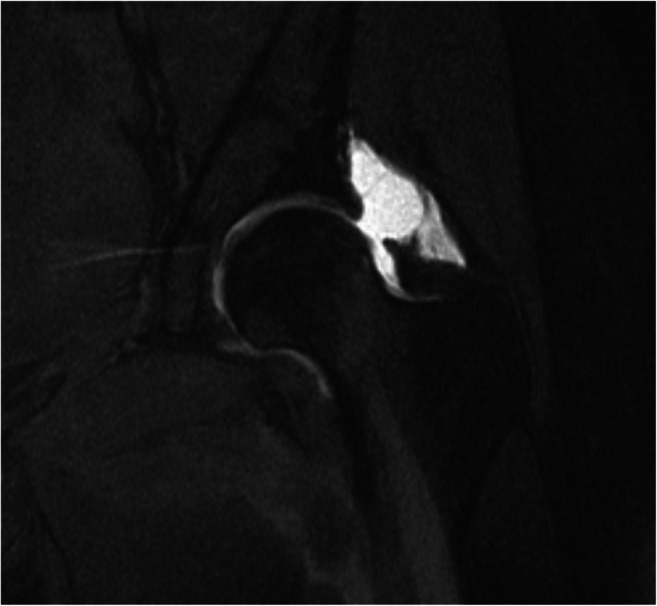

Fig. 2.

Coronal MRI image slice (T1-weighted fat-suppressed) demonstrating a large capsular defect present in the anterosuperior region of the hip capsule with substantial extravasation of fluid indicative of capsular insufficiency

MRA imaging with contrast injected into the peripheral hip compartment clearly delineates the synovial surface of the hip capsule to provide valuable diagnostic information regarding the integrity and morphology of the surgically altered hip capsule [52] (Fig. 2). The region of primary interest when evaluating for hip capsular pathology in the revision setting is the anterosuperior hip capsule, approximately 12 to 3 o’clock, in the region of the previous capsulotomy (Fig. 3). Several studies have aimed to evaluate the clinical utility of magnetic resonance imaging assessment of capsular integrity.